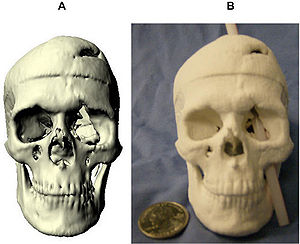

Accuracy of Open-Source Software Segmentation and Paper-based Printed Three-Dimensional Models

|

Publication: J Craniomaxillofac Surg. 2016 Feb;44(2):202-9. PMID: 26748414 Authors: Szymor P, Kozakiewicz M, Olszewski R. Institution: Department of Maxillofacial Surgery, Medical University of Lodz, Lodz, Poland. Background/Purpose: In this study, we aimed to verify the accuracy of models created with the help of open-source 3D Slicer 3.6.3 software (Surgical Planning Lab, Harvard Medical School, Harvard University, Boston, MA, USA) and the Mcor Matrix 300 paper-based 3D printer. Our study focused on the accuracy of recreating the walls of the right orbit of a cadaveric skull. Cone beam computed tomography (CBCT) of the skull was performed (0.25-mm pixel size, 0.5-mm slice thickness). Acquired DICOM data were imported into 3D Slicer 3.6.3 software, where segmentation was performed. A virtual model was created and saved as an .STL file and imported into Netfabb Studio professional 4.9.5 software. Three different virtual models were created by cutting the original file along three different planes (coronal, sagittal, and axial). All models were printed with a Selective Deposition Lamination Technology Matrix 300 3D printer using 80 gsm A4 paper. The models were printed so that their cutting plane was parallel to the paper sheets creating the model. Each model (coronal, sagittal, and axial) consisted of three separate parts (∼200 sheets of paper each) that were glued together to form a final model. The skull and created models were scanned with a three-dimensional (3D) optical scanner (Breuckmann smart SCAN) and were saved as .STL files. Comparisons of the orbital walls of the skull, the virtual model, and each of the three paper models were carried out with GOM Inspect 7.5SR1 software. Deviations measured between the models analysed were presented in the form of a colour-labelled map and covered with an evenly distributed network of points automatically generated by the software. An average of 804.43 ± 19.39 points for each measurement was created. Differences measured in each point were exported as a .csv file. The results were statistically analysed using Statistica 10, with statistical significance set at p < 0.05. The average number of points created on models for each measurement was 804.43 ± 19.39; however, deviation in some of the generated points could not be calculated, and those points were excluded from further calculations. From 94% to 99% of the measured absolute deviations were <1 mm. The mean absolute deviation between the skull and virtual model was 0.15 ± 0.11 mm, between the virtual and printed models was 0.15 ± 0.12 mm, and between the skull and printed models was 0.24 ± 0.21 mm. Using the optical scanner and specialized inspection software for measurements of accuracy of the created parts is recommended, as it allows one not only to measure 2-dimensional distances between anatomical points but also to perform more clinically suitable comparisons of whole surfaces. However, it requires specialized software and a very accurate scanner in order to be useful. Threshold-based, manually corrected segmentation of orbital walls performed with 3D Slicer software is accurate enough to be used for creating a virtual model of the orbit. The accuracy of the paper-based Mcor Matrix 300 3D printer is comparable to those of other commonly used 3-dimensional printers and allows one to create precise anatomical models for clinical use. The method of dividing the model into smaller parts and sticking them together seems to be quite accurate, although we recommend it only for creating small, solid models with as few parts as possible to minimize shift associated with gluing. |